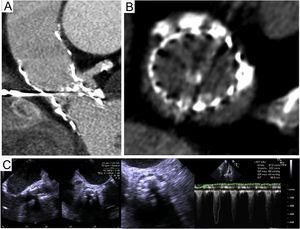

The patient was a 71-year-old man with severe aortic stenosis and coronary artery disease diagnosed in 2008. At the time, he had intermediate surgical risk but nevertheless refused surgery as a therapeutic option. Percutaneous revascularization was therefore undertaken, with implantation of a 26-mm CoreValve aortic prosthesis. The patient was free of symptoms with stable gradients until 2016, when the gradients started to increase, and symptoms reappeared in November 2017. Computed tomography angiography and ultrasound study showed signs of prosthesis degeneration, leaflet calcification (Figure 1A), leaflet thickening (Figures 1B and C) and increased gradient (Figure 1C). When the patient was aged 81 years, a 26-mm CoreValve Evolute Pro was successfully implanted in the existing prosthesis. Figure 2 (TAVI, transcatheter aortic valve implantation) shows details of the procedure and the hemodynamic changes in the aorta (Ao), left ventricle (LV), and pulmonary artery (PA). It has been shown that surgical biological prostheses that have undergone degeneration can be successfully treated with percutaneous aortic prostheses. However, there is no information on percutaneous prosthesis degeneration after 10 years, given that survival in recipients of such prostheses is lower and so such events are rare. To our knowledge, this is the first published case of a self-expanding prosthesis with degeneration 10 years after implantation that was treated with another percutaneous prosthesis. It demonstrates that this is a feasible and safe approach. If outcome is confirmed, this case could help to extend the indication for percutaneous prostheses to patients with intermediate risk.